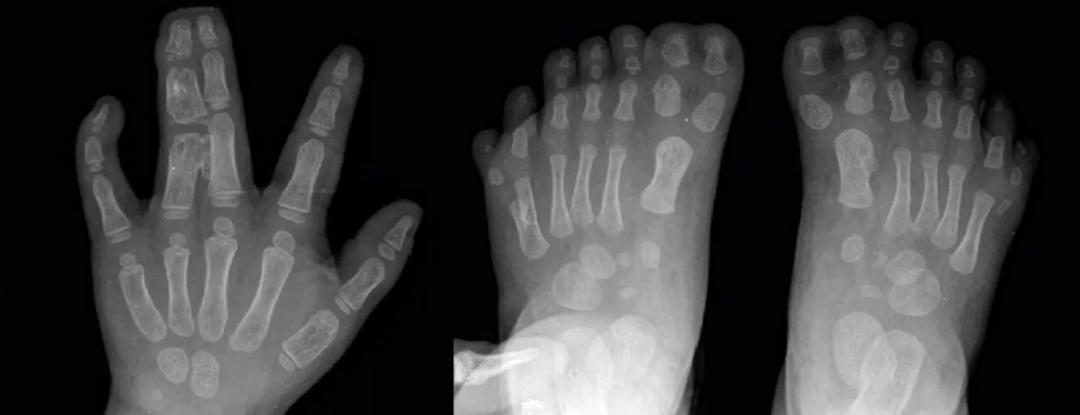

这些后代几乎都出现 身高不足、多指和并指等畸形问题 ,如今这些族人因为*亲近**繁殖已经濒临灭绝。

畸形的手指、脚趾